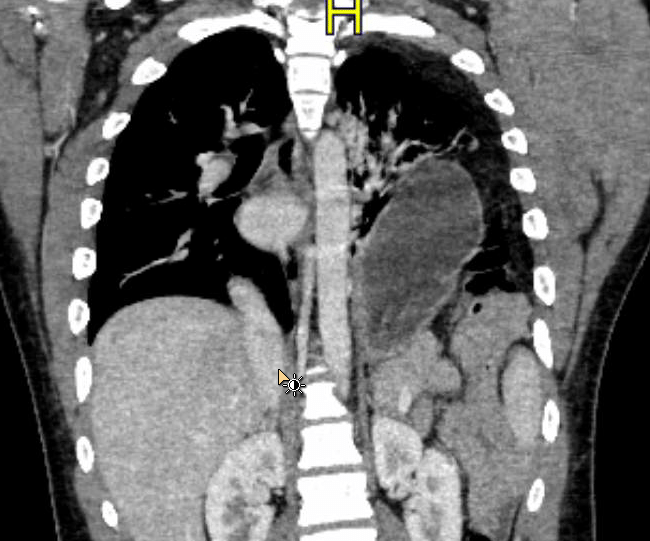

Age: 21

Sex: Male

Indication: Trauma

Sample ReportPoor definition of the left hemidiaphragm with abdominal contents overlying the left lung base. These findings raise concern for diaphragmatic rupture in the setting of trauma. Recommend CT for further evaluation.

Associated rightward mediastinal shift.

Hazy left basilar opacities likely relate to atelectasis, aspiration, and/or contusion.

No pleural effusion or pneumothorax.